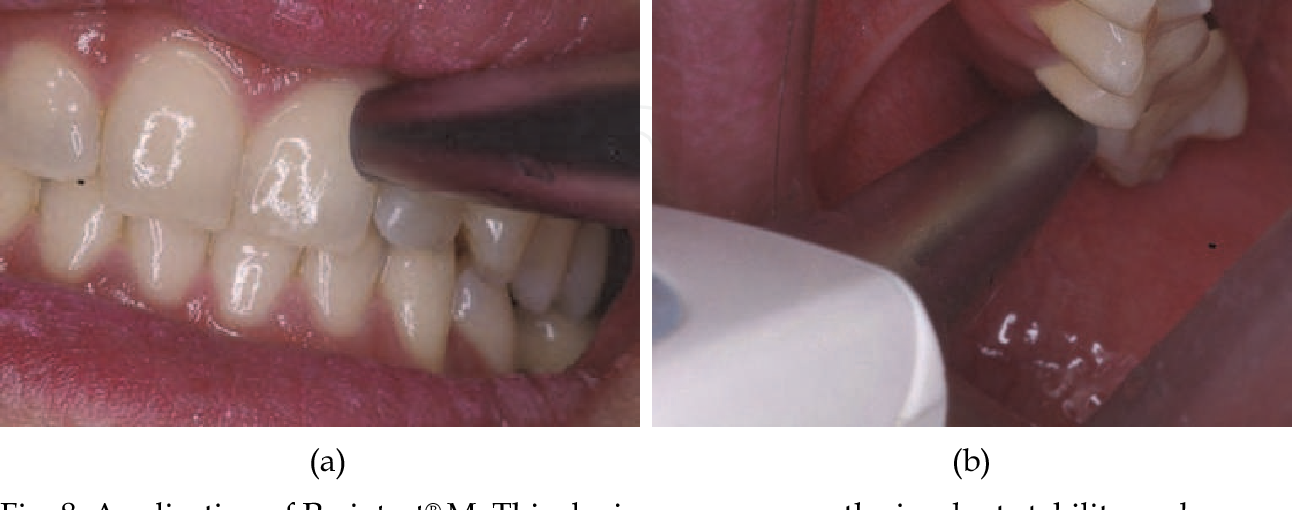

How long does it take for dental implants to settle?

How long does it take to install the teeth to settle? It takes an average of six to eight months for implanted teeth to fully heal to the point where you can resume your daily routine without help.